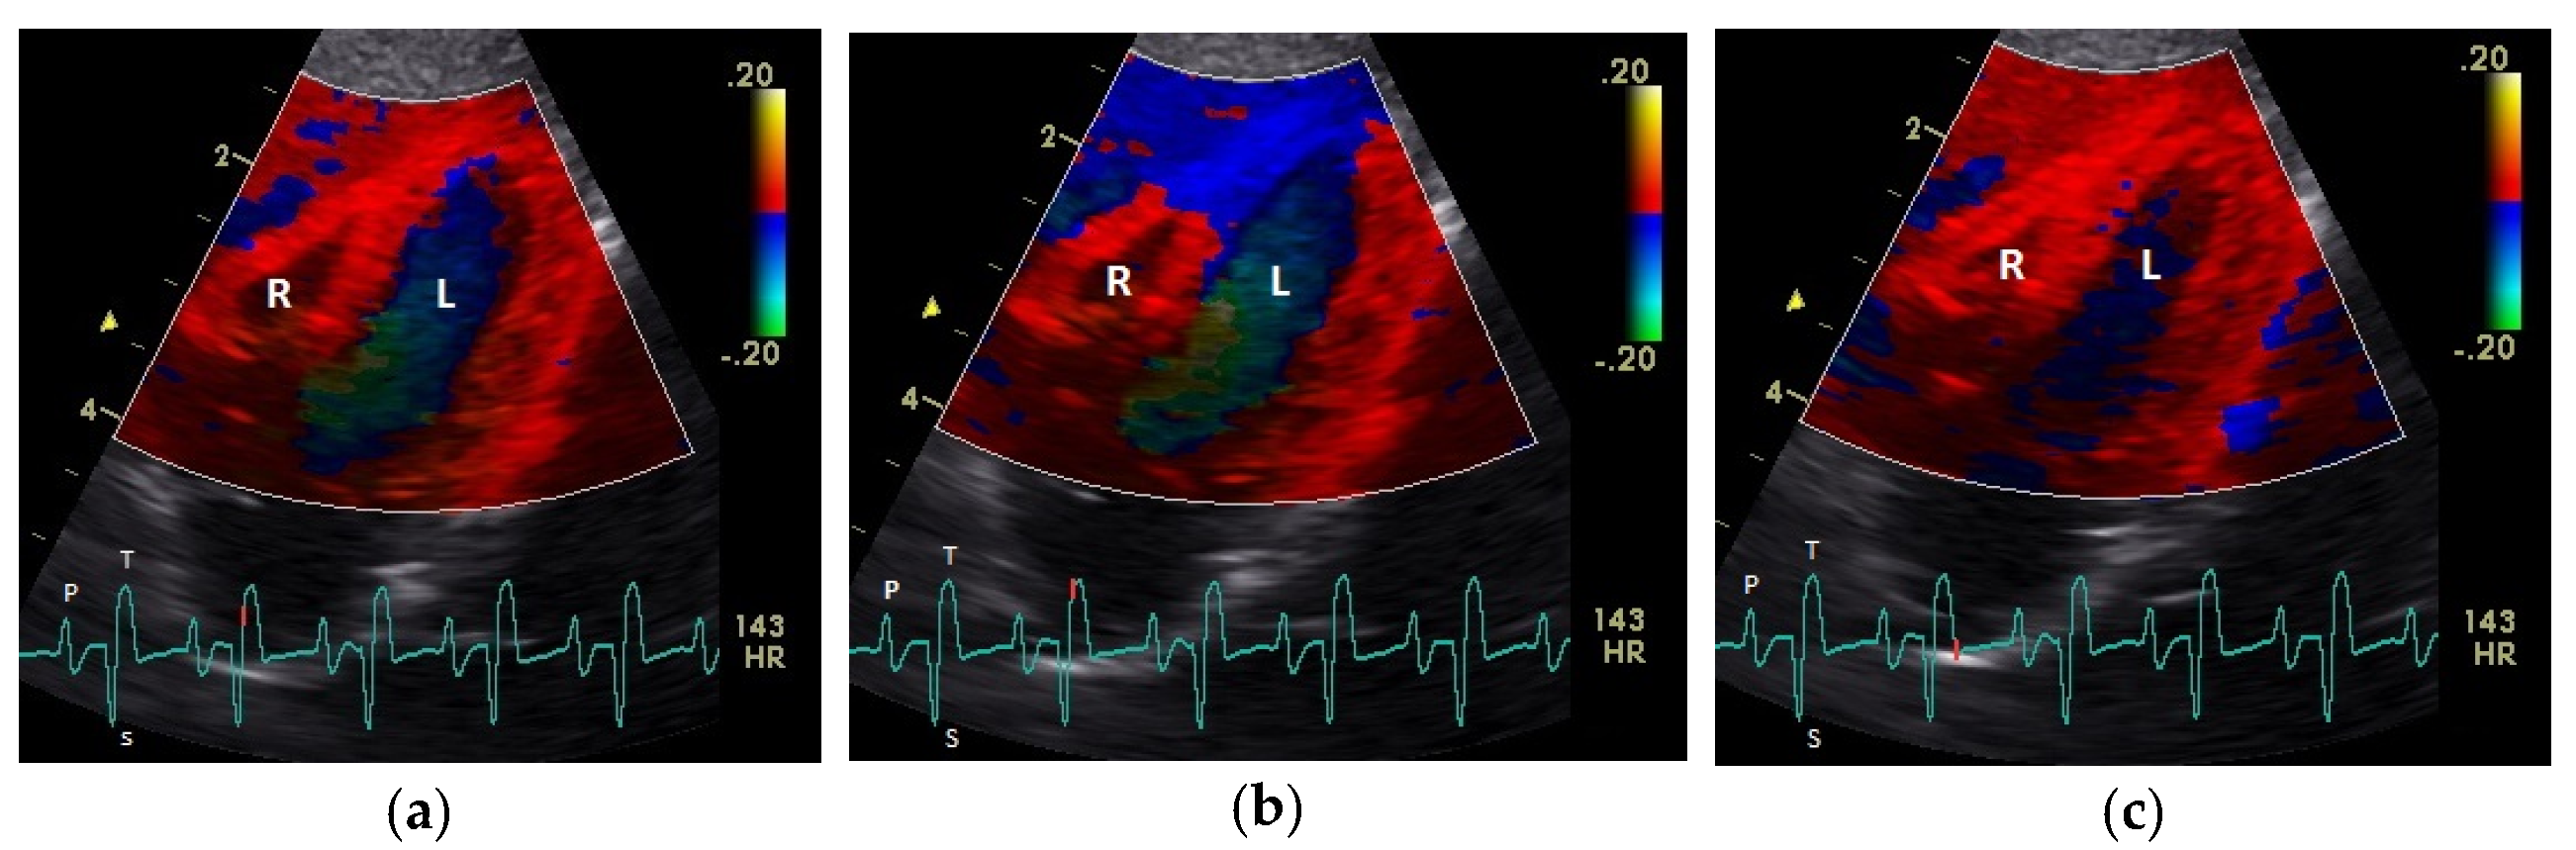

Figure 2.

Color coding of the early (a), middle (b), and late part (c) of systolic tissue velocities by tissue Doppler imaging from the four-chamber view: the movement of the myocardium toward (red color) and away from the heart apex (blue color) is visible. R: right; L: left ventricle; HR: heart rate. Electrocardiogram: P: P wave; S: S wave; T: T wave. The color scale on the right of the image is calibrated in cm s−1.

The positive S’ wave of the TDI curve (Figure 3 and Figure 4; ascending part of the S wave to the descending part of the T wave of the ECG) describes the systolic movement of the heart base toward the heart apex and represents the expulsion phase of the heart. In the middle of the S’ wave of the TDI, there is little movement of the heart apex toward the heart base and the myocardial velocities are negative (Figure 2). This movement in the middle part of the systole led to an irregular shape of the S’ wave in the TDI curve (Figure 3). The negative E’ wave (Figure 3 and Figure 4; after the T wave of the ECG) in the TDI curve describes the movement of the myocardium during the passive ventricular filling and the second negative A’ wave of the TDI curve (Figure 3 and Figure 4; P wave of the ECG) describes the movement of the myocardium in the active filling phases of the heart during the diastole away from the heart apex. Before and after the S’ wave, the TDI curve showed undirected deflections as a sign of isovolumetric contraction (IVC) and relaxation (IVR; Figure 3 and Figure 4). However, the transition between the A’ and S’ waves (IVC) and the S’ and E’ waves (IVR) could be flowing and sometimes difficult to see.